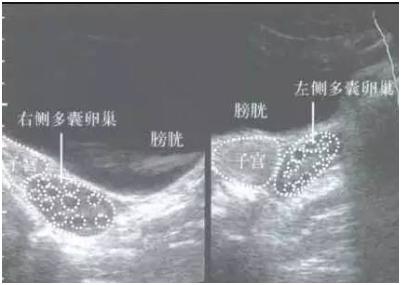

超声检查时的异常表现:

B超检查时可见多个不成熟的小卵泡呈串珠状包绕于卵巢周边,多大于10~12个,俗称“项链征”。